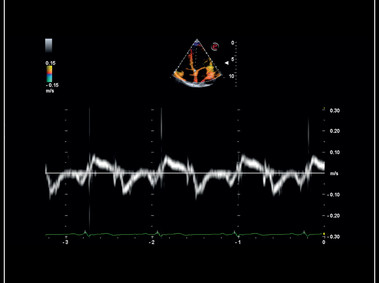

Siêu âm Doppler mô cơ tim với TVM

TVM – Myocardial tissue doppler velocity